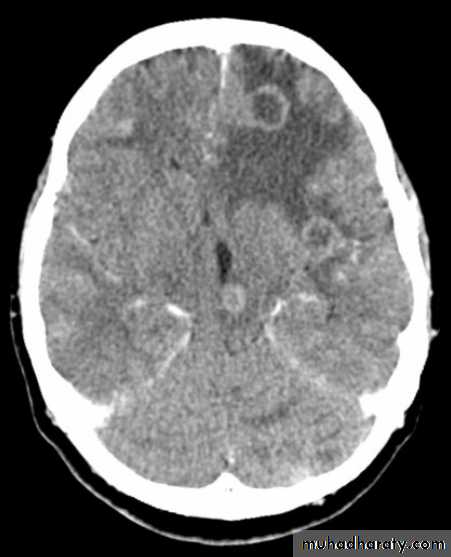

Secondary metastasis

Old age group above 50 Y , any lesion within the cerebellar hemisphere it is secondary metastasis unless proven otherwise F. from breast CA M. from bronchogenic CA .

Appear as nodular single or multiple lesion hypo dense or hyper dense .

Surrounded by per focal edema

Enhanced as solid or ring pattern of enhancement .